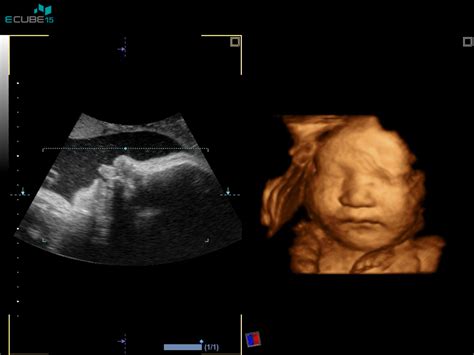

Tri- in štiridimenzionalni ultrazvok: Vizualizacija v novi dimenziji

Poleg standardnega dvodimenzionalnega (2D) ultrazvoka, ki daje črno-bele prereze, obstajata tudi 3D in 4D ultrazvok.

- 3D ultrazvok: Ta tehnika ustvari tridimenzionalno računalniško rekonstrukcijo slike iz serije zaporednih 2D slik. Omogoča boljše merjenje volumnov in prikazovanje telesnih značilnosti ploda v prostoru, kar staršem pomaga pri boljši predstavi o videzu otroka.

- 4D ultrazvok: Dodaja časovno komponento k 3D sliki, kar omogoča opazovanje gibanja ploda v realnem času.

Čeprav 3D/4D ultrazvok ponuja vizualno bogatejše izkušnje, njegova diagnostična vrednost v primerjavi z 2D ultrazvokom ni vedno bistveno večja, razen pri določenih specifičnih ocenah. Pogosto se uporablja za prikazovanje določenih delov plodovega telesa staršem. Zavedati se je treba, da so ti pregledi pogosto samoplačniški.